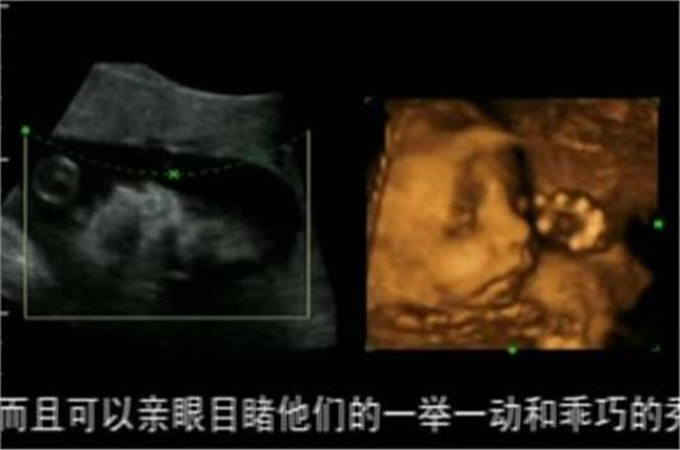

大概在五个月的时候,在老公的陪同下张女士去做了产检,通过仪器的照片可以看到宝宝的样子,没想到让张女士感到很尴尬,四维照下的宝宝原型毕露,和自己想象的完全不一样。宝宝的鼻子和嘴比较平而且还很小,最关键的是头像看起来不太标准,至于长的像谁看不出来,不过可以肯定的一点是有点丑。

四维照给人感觉和现实不太一样,感觉一点都不真实,只能看到大概的轮廓,而且也是隐隐约约的,张女士本来以为可以看到一个帅气的宝宝,哪怕是稍微可爱一点也可以,结果一点都没让自己满意。反正孩子现在还在发育中,相信将来孩子出生的时候一定不会让自己失望的。

宝宝在发育不全的时候看起来会有点丑,这是正常的情况,毕竟离出生的时间还有些距离,不能长到成熟的样子,通过四维照看到的宝宝也不完全是清晰的,可能会有些偏差,所以看起来会觉得有点丑,不用太放在心上。

角度不一样的时候看到的结果也不同,这是因为四维照从不同的角度把他们合成之后,你才能看到眼前的结果,有时候看到的结果确实是最丑的角度,只能看到一个大概的样子,另外宝宝的环境是在羊水中,也会显得样子模糊。